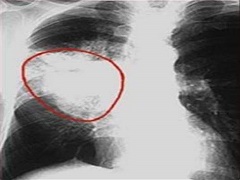

在一项开放标签、Ⅲ期试验中,以1∶1的比例,将既往未接受过ALK抑制剂治疗的晚期ALK阳性NSCLC患者随机分组,分别接受布加替尼180 mg,1次/d或克唑替尼250 mg,2次/d。主要终点为无进展生存期(PFS),次要终点包括客观缓解率和颅内缓解率。275例患者被随机分为两组:137例为布加替尼组,138例为克唑替尼组。第一次中期分析时,布加替尼组和克唑替尼组的中位随访时间分别为11.0个月和9.3个月。布加替尼组12个月无进展生存期的比例为67%,高于克唑替尼组的43%(P<0.001)。布加替尼组和克唑替尼组的客观缓解率分别为71%(95% CI为62~78)和60%(95% CI为51~68);在有可测量病变的患者中,经证实的颅内缓解率分别为78%(95% CI为52~94)和29%(95% CI为11~52)。未发现新的安全性问题。

以上研究表明:在既往未接受过ALK抑制剂治疗的ALK阳性NSCLC患者中,接受布加替尼治疗患者的无进展生存期明显优胜于接受克唑替尼治疗的效果。所以在治疗过程中,布加替尼被推介的频率较高。有问题请咨询海得康海外就医。